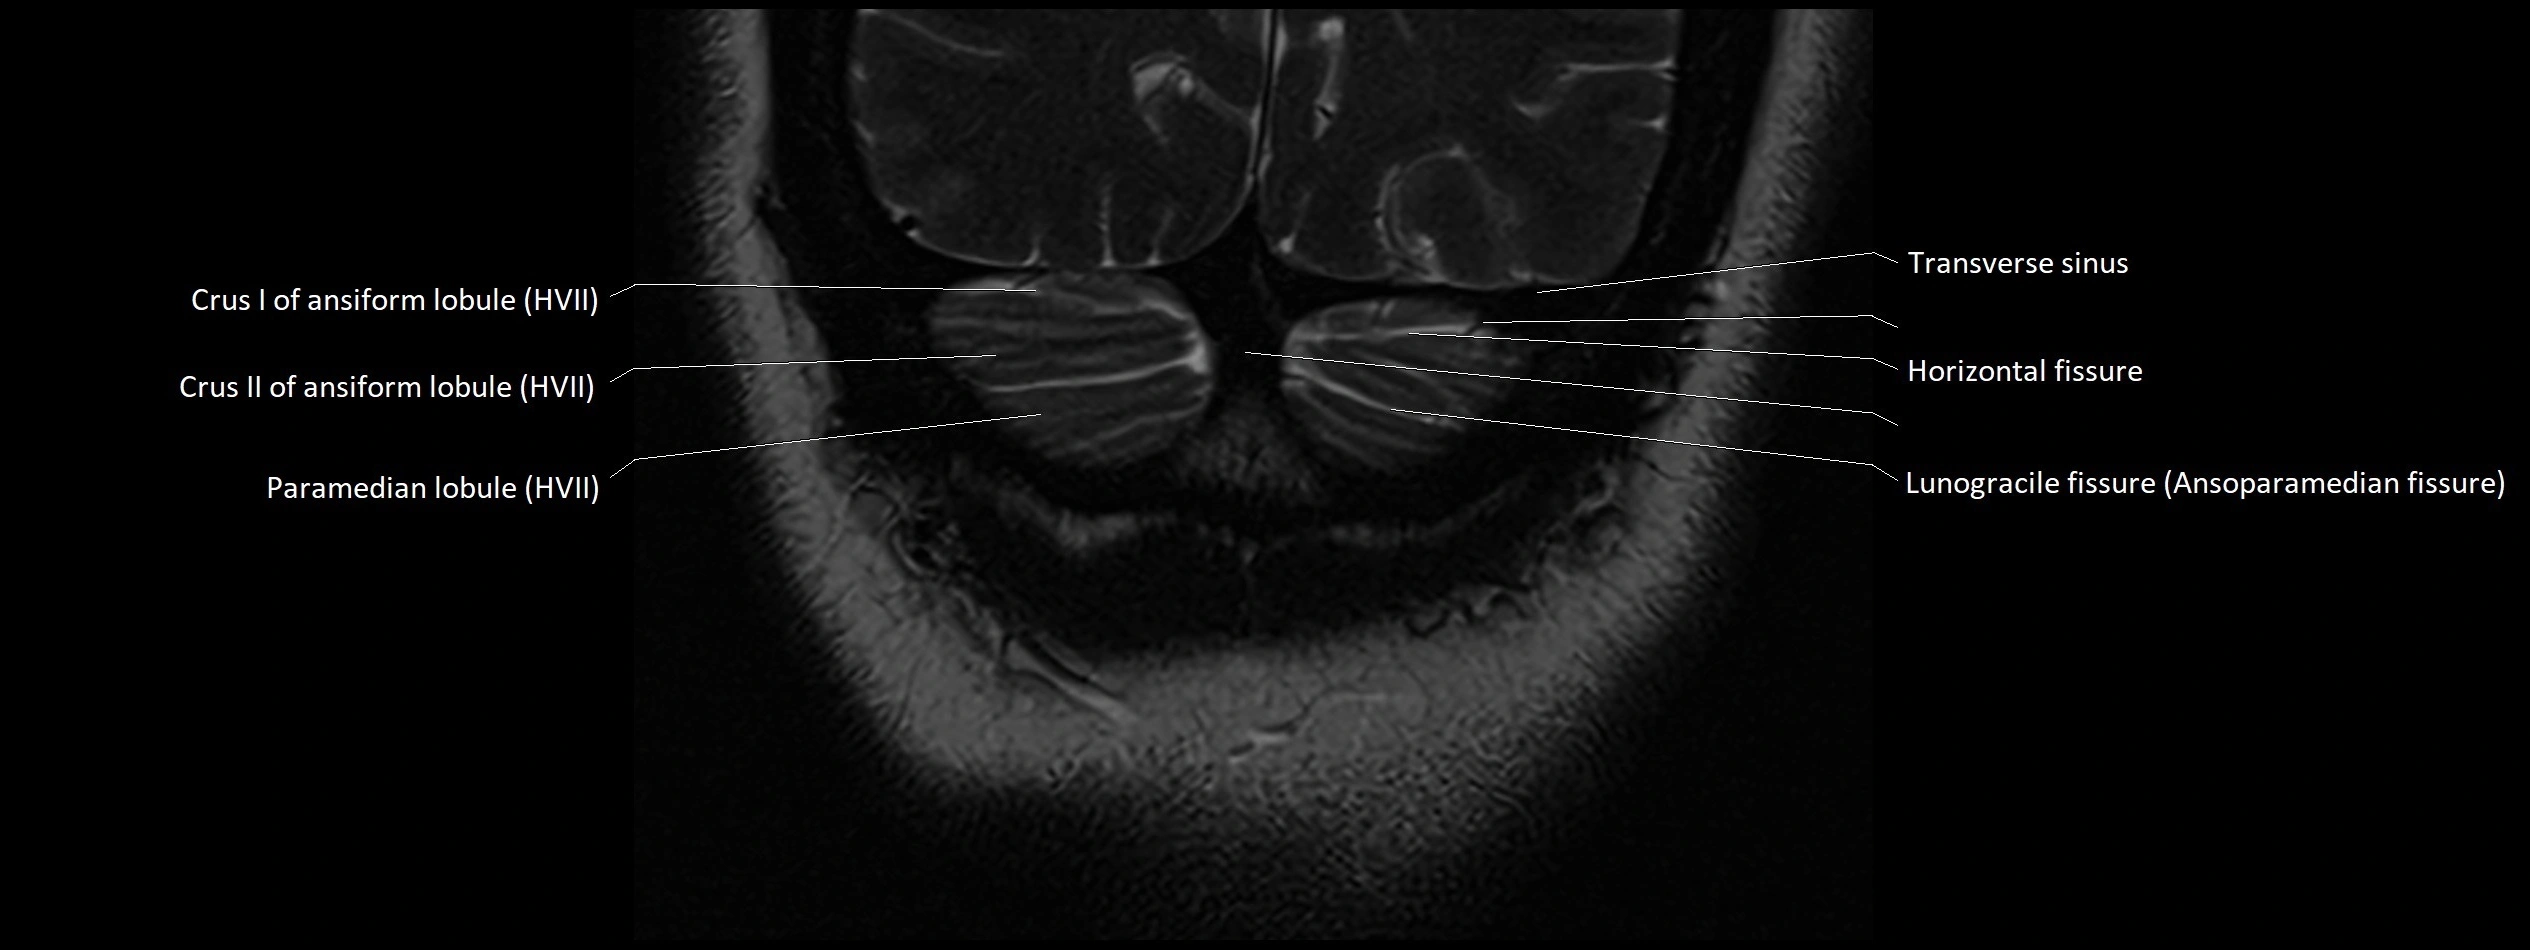

- Crus I of ansiform lobule of cerebellum

- Crus II of ansiform lobule of cerebellum

- Horizontal fissure (cerebellum)

- Lunogracle fissure

- Lunogranicile fissure of cerebellum

- Paramedian lobule (HVII) of cerebellum

- Transverse sinus